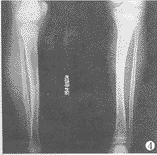

图3 骨延长4.2cm,骨缺损、骨不连处骨性愈合,双下肢等长(图右侧为患肢)